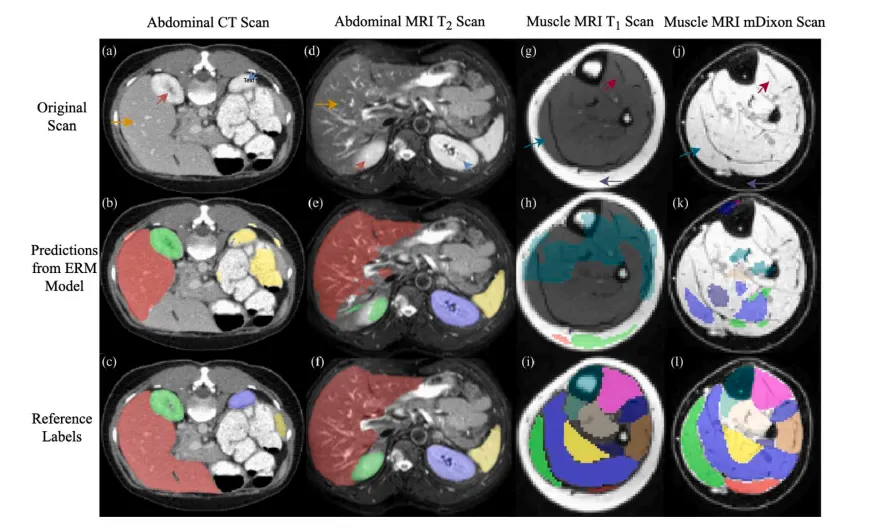

近年来,深度神经网络在医学图像分析等多个图像处理与计算机视觉领域取得了前所未有的进展(Litjens等,2017)。特别是,卷积神经网络(CNN)等模型在表征学习能力方面表现出色,达到甚至超越了人类专家在多种视觉任务中的表现,前提是以监督方式进行训练(Yann等,2015)。然而,监督模型需要大量标注数据进行训练,这限制了其在医学图像任务中的应用,因为生成像素级标注的成本非常高。此外,监督模型在实际部署时,通常会面临来自不同于训练数据分布的目标域的新测试样本,从而导致推理性能下降。在此,“域”指的是由特定数据收集协议和背景定义的数据分布。在医学成像中,不同的域可能包含不同模态的数据(图1(a,d)),或者是相同模态但由不同站点或不同采集参数获取的数据。不同域数据之间常存在显著的分布差异和图像外观差异。例如,T1加权MRI和mDixon MRI扫描对于相同的解剖结构呈现出不同的对比度(图1(g,j))。这种训练域与测试域之间的偏差,被称为域漂移,在医学图像任务中很常见(Ben-David等,2010),这不仅妨碍了训练模型的共享,还需要跨数据集重新训练,限制了深度神经网络在预算和时间受限场景下的使用。

CTTA可用于对纵向研究中在不同时间点采集的医学图像进行分割,但适配的前提是源模型(通常通过经验风险最小化(ERM) 训练)在目标域上已经具有一定的性能(图1(a-f))。然而,ERM模型在严重的域漂移情况下往往难以提供足够的适应性能(图1(g-l))。可以利用领域知识设计预处理过程,以减少域间差距,使ERM模型在目标域上表现良好(Kim和Chai,2021)。然而,当一个预训练模型需要共享给多个终端用户以适配不同测试时数据分布时,设计预处理过程的工作量会显著增加。

Fig. 1. Demonstrations of different severities of domain shifts. Example 1: panels (a) and (d) are CT and MRI T2 scans containing the same abdominal structures, © and (f) aretheir segmentation ground truth labels, and (b) and (e) are cross-domain predictions for (a) and (d) by an ERM model trained on (d) and (a), respectively. Example 2: panels (g)and (j) are MRI T1 and mDixon scans containing the same musculoskeletal structures, (i) and (l) are their segmentation ground truth labels, and (h) and (k) are labels predictedfor (g) and (j) by an ERM model trained on (j) and (g), respectively. Arrows of the same color indicate the same anatomical structures across different domains.

图1. 不同域漂移严重程度的示例。 示例1:面板(a)和(d)分别为包含相同腹部结构的CT和MRI T2扫描图像,©和(f)是它们的分割真实标签,(b)和(e)是ERM模型分别在(d)和(a)上训练后对(a)和(d)的跨域预测结果。 示例2:面板(g)和(j)分别为包含相同骨骼肌结构的MRI T1和mDixon扫描图像,(i)和(l)是它们的分割真实标签,(h)和(k)是ERM模型分别在(j)和(g)上训练后对(g)和(j)的预测结果。 相同颜色的箭头指示在不同域中相同的解剖结构。